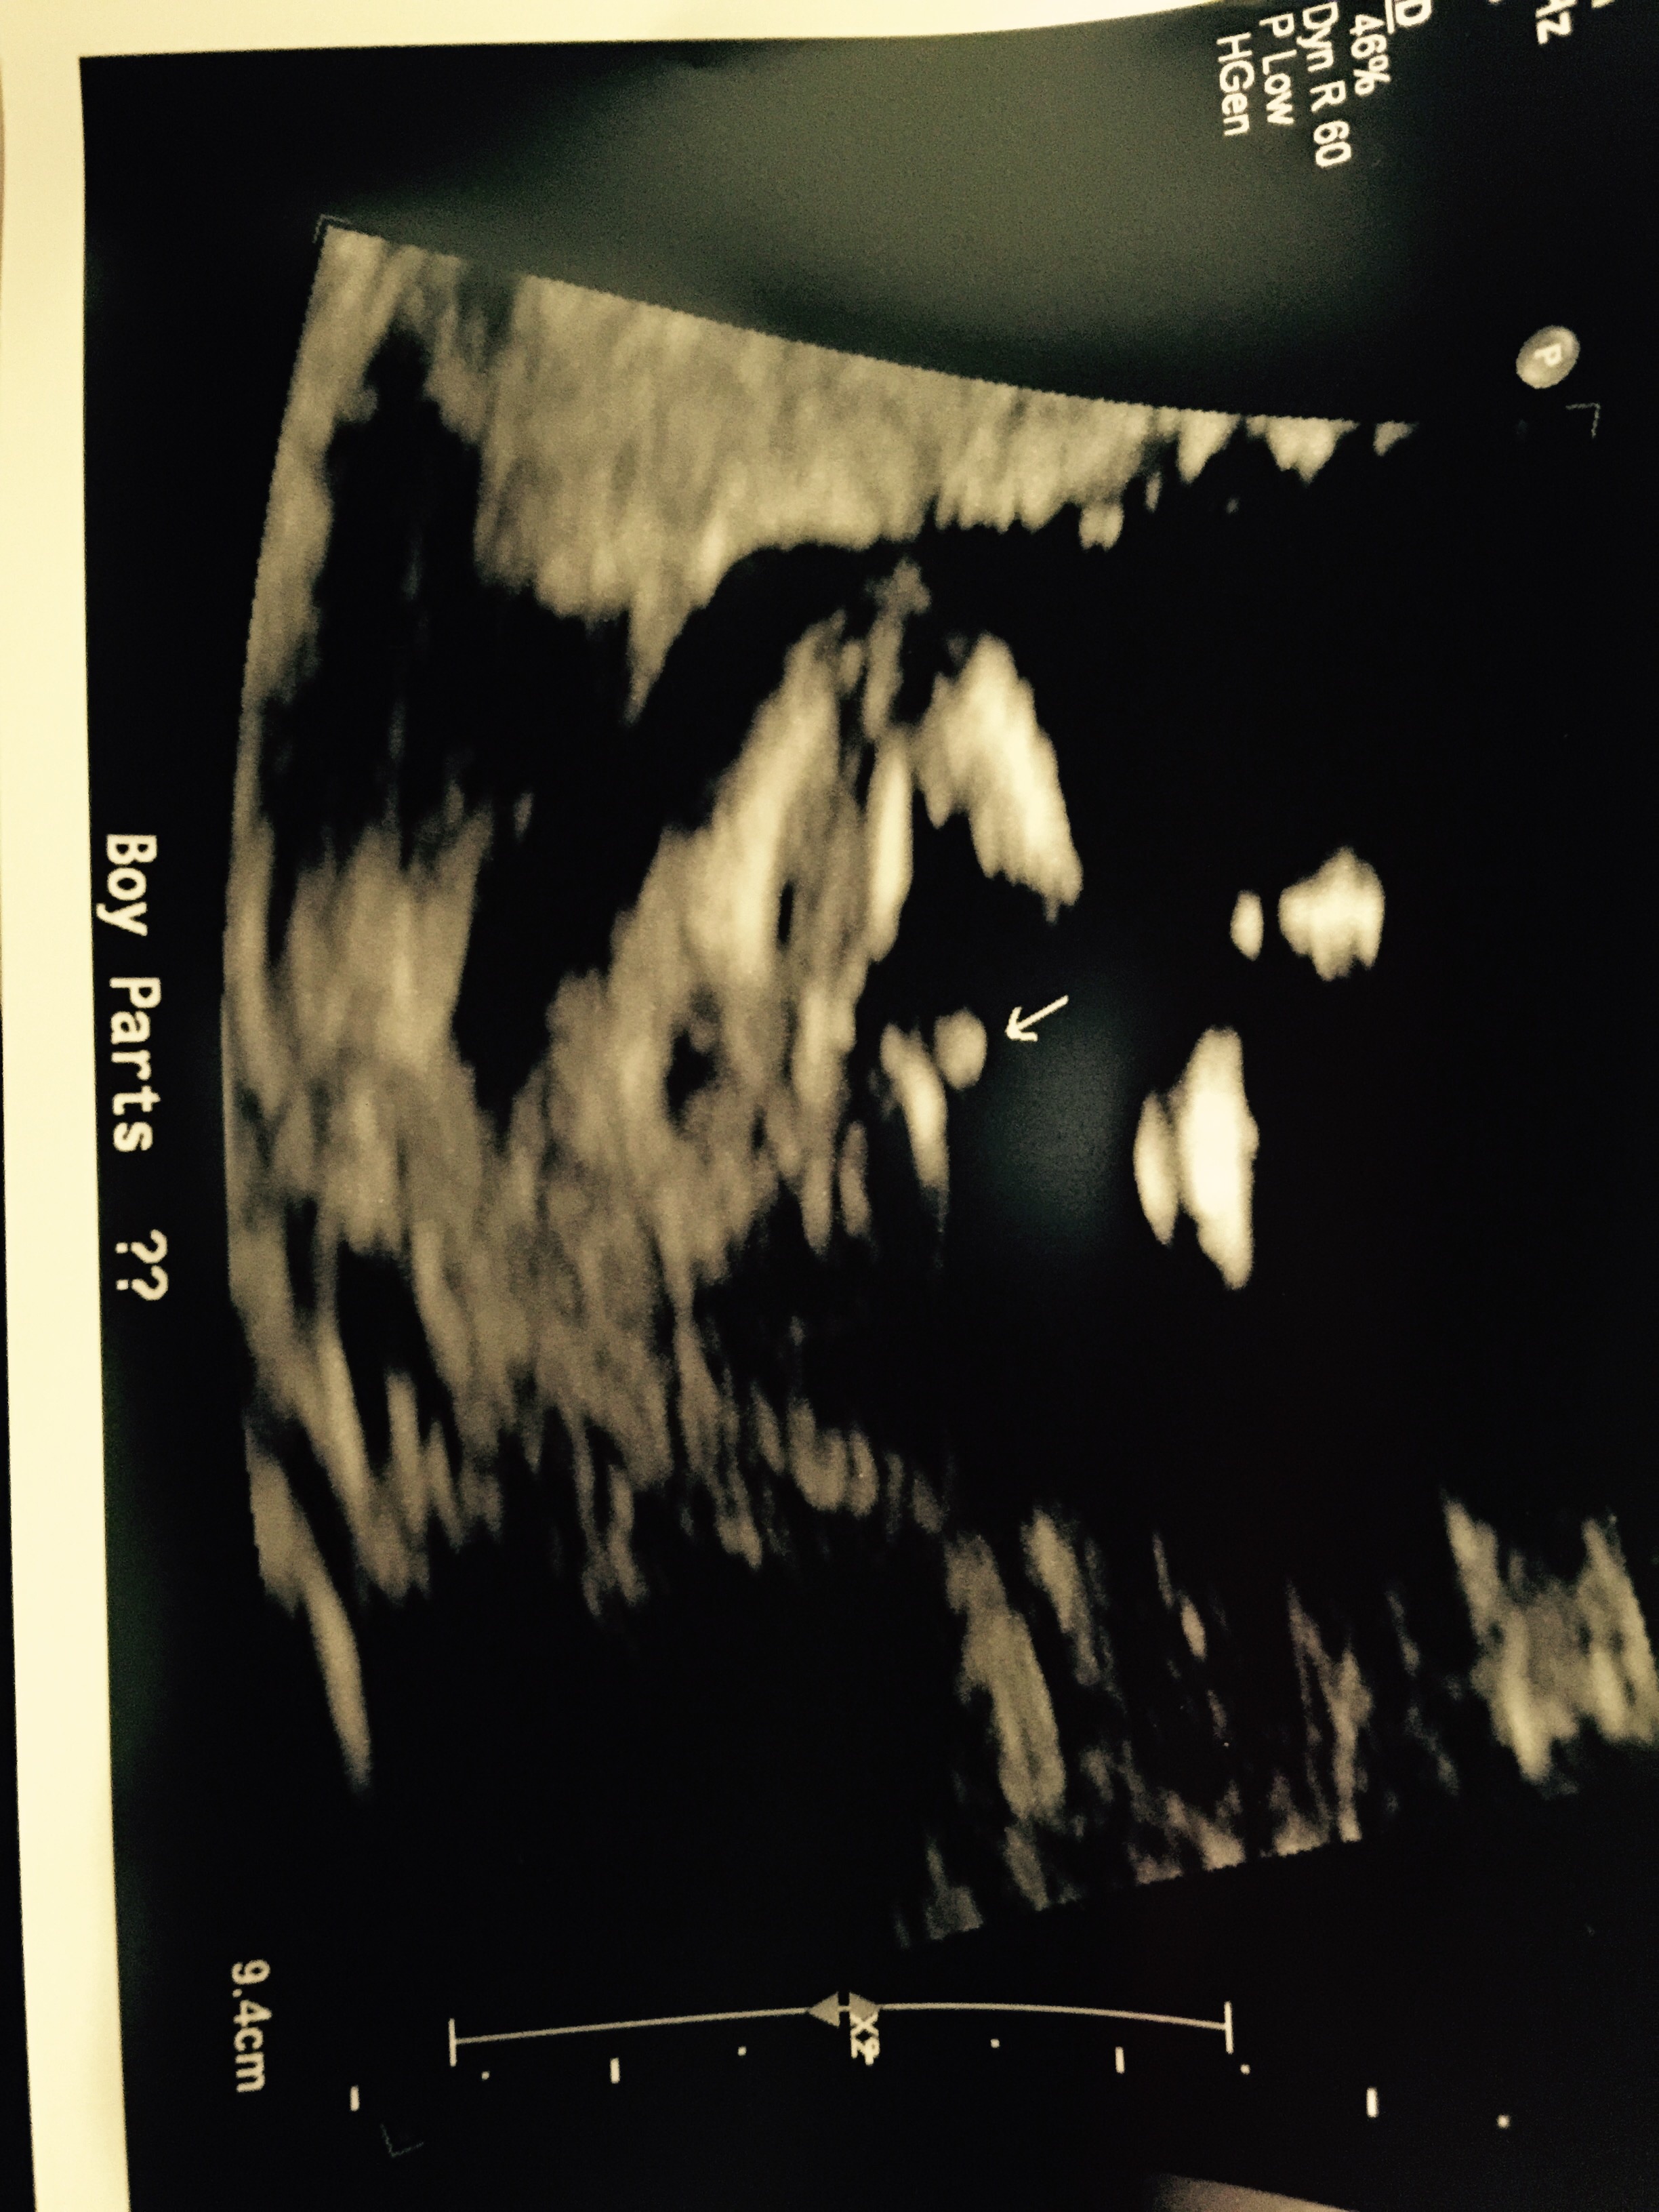

Just got back from my week 15 anatomy scan, sonographer said she was 70% certain it was a boy!!

What do you think?

Week 15 anatomy scan!! Boy parts??

Looks a lot like a boy! Congrats!

Baby blue

Before I get to involved with baby boy names, is there any chance it's genitals are swollen and the baby could be baby pink? Or is it looking all boy? Thanks!!